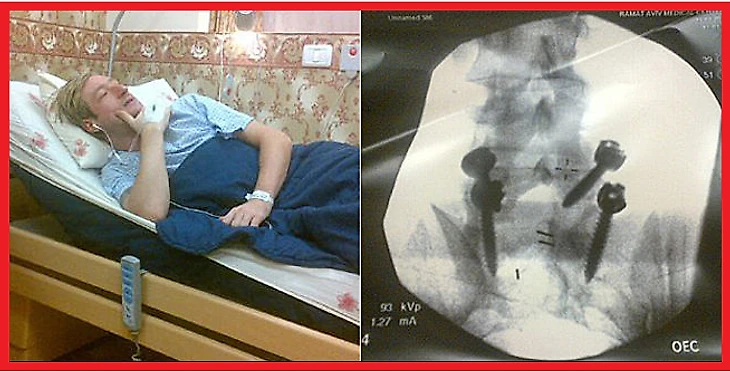

Почётное первое слово дадим трёхкратной олимпийской чемпионке в парном катании Ирине Родниной: «Когда приземляешься с прыжка, позвоночник принимает удар весом от 600 до 800 килограммов. Мы же приземляемся на одну ногу, весь корпус перекошен. Причем делаем это годами. У ребят-фигуристов, которым 18-19 лет, тазобедренный сустав как у 80-летних. Родители, к сожалению, не понимают, что профессиональный спорт диктует свои условия».

Не знаю, можно ли считать олимпийских чемпионов по фигурному катанию Алексея Ягудина, Евгения Плющенко и Юдзуру Ханю «неготовыми физически спортсменами», но только специалисты утверждают, что даже в тройном прыжке спортсмен испытывает нагрузку в 10 g, то есть в десять раз превышающую вес его тела! Космонавты при спуске с орбиты испытывают нагрузку 4 - 6 g ---- вдвое меньше!

Но даже если представить себе такие идеальные условия, когда спортсмену везёт и он никогда серьёзно не травмируется, из-за специфического характера нагрузок в парном и одиночном катании это всё равно не проходит бесследно. Ведь фигуристы скручивают элементы всегда в одну сторону: кто-то всегда вращается по часовой стрелке, кто-то --- против, но приземление всегда идёт на одну ногу. Кости и суставы этой ноги каждый раз испытывают перегрузки, превышающие вес спортсмена в несколько раз. «Прыжки и вращения рано или поздно скажутся на асимметричном строении тела фигуриста, --- пишет Леонид Райцин в своей книге "Время спортивных технологий". --- От того, что работа идет всё время в одну сторону, искривление позвоночника --- обязательная болезнь у фигуристов».